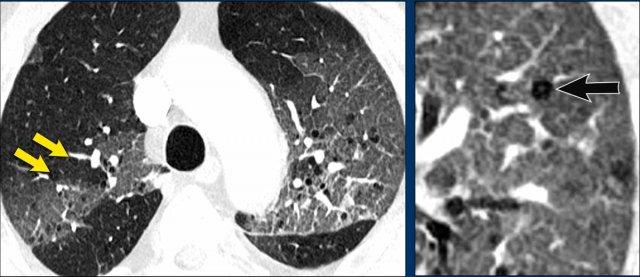

Khi có nhiều hình ảnh trông giống nang, cần phân biệt bệnh phổi dạng nang thực sự với các bệnh lý bắt chước khác (hình minh họa).

- Nhiều nang phổi với thành mỏng ở bệnh nhân LCH giai đoạn tiến triển. Đây là bệnh phổi dạng nang thực sự.

- Khí phế thũng trung tiểu thùy, biểu hiện là các lỗ đen không có thành. Lưu ý dấu hiệu chấm trung tâm (mũi tên). Khí phế thũng có thể là yếu tố gây nhầm lẫn thực sự và sẽ được thảo luận chi tiết hơn ở phần sau.

- Tổ ong (Honeycombing) biểu hiện là chồng các nang thành dày ở ngoại vi thùy dưới ở bệnh nhân xơ phổi.

- Giãn phế quản dạng nang, biểu hiện là các ống dạng nang. Thường không khó phân biệt khi cuộn qua các lát cắt, nhưng đôi khi có thể gây thách thức.